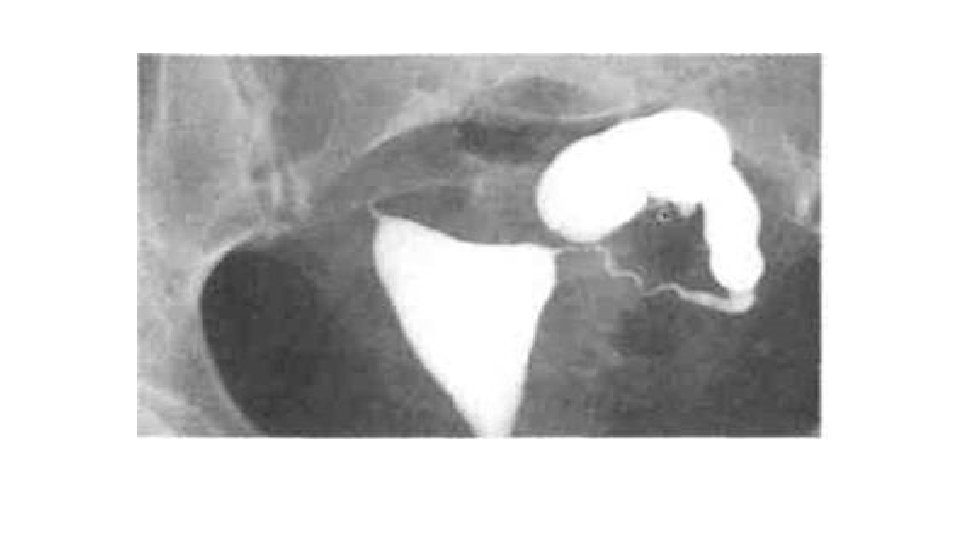

Chronic PID - Chronic inflammation may result in occlusion of one or both ends of the tube, accumulation of fluid within the tubal lumen, tubal distension serous fluid hydrosalpinx purulent fluid pyosalpinx - Healing of the inflamed pelvic structures will result in adhesion formation mainly posterior to the uterus. These adhesions may be: mild severe

Chronic PID Investigations: . Pelvic ultrasound fixed RVF uterus, cystic pelvic mass . HSG tubal obstruction, hydrosalpinx . D laparoscopy pelvic adhesions (frozen pelvis) pelvic mass